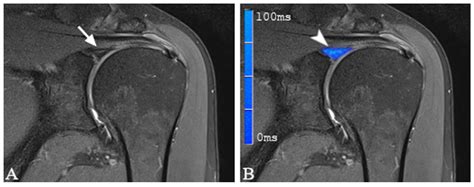

• Imaging Tests: Magnetic Resonance Imaging (MRI) is the gold standard for diagnosing Slap Tear Types. An MRI arthrogram, which involves injecting contrast dye into the shoulder joint, can provide more detailed images of the labrum and surrounding structures.